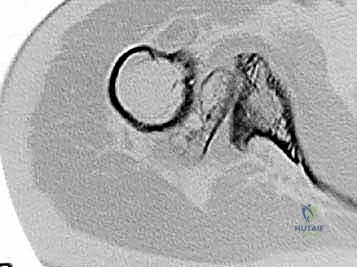

Radiographic findings in primary osteoarthritis include subchondral sclerosis and cyst formation, osteophyte formation, and asymmetrical posterior joint space narrowing ( FIG 4A,B ). 20

A B

A

B C

FIG 4 • Radiographic findings in osteoarthritis include osteophyte formation, especially on the inferior humerus as seen on the AP view ( A ), and asymmetrical posterior glenoid wear with posterior subluxation, as seen on the axillary view ( B ). C. CT scan reveals a large inferior humeral osteophyte and a type C glenoid, with increased glenoid retroversion. D. Coronal MR image in a patient with rheumatoid arthritis reveals an intact but very thin rotator cuff with erosion of the humeral attachment site, and evidence of rotator cuff dysfunction (ie, proximal humeral migration).

D

Computed tomographic (CT) scans are helpful in quantifying bone loss in patients with posterior subluxation ( FIG 4C ).

MRI is useful in patients with rheumatoid arthritis to determine rotator cuff integrity ( FIG 4D ).